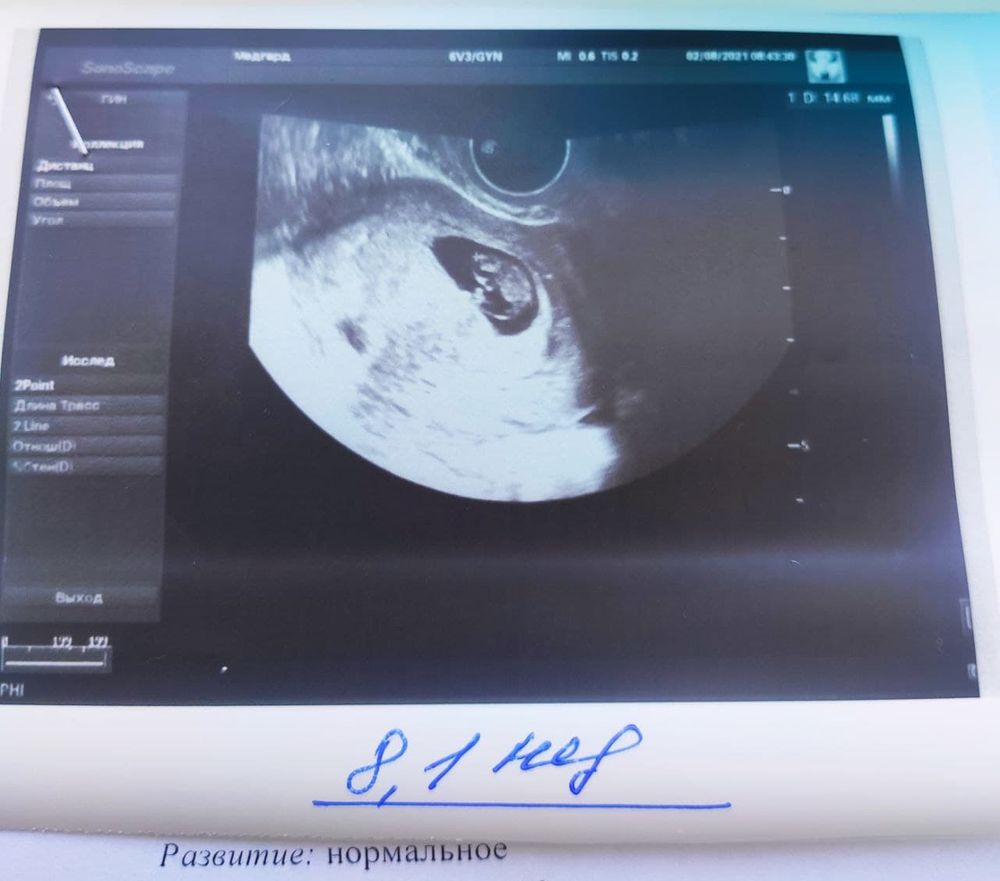

УЗИ 8нед1день - красивая лялечка

Какая красота! Растите и крепчайте ! :))